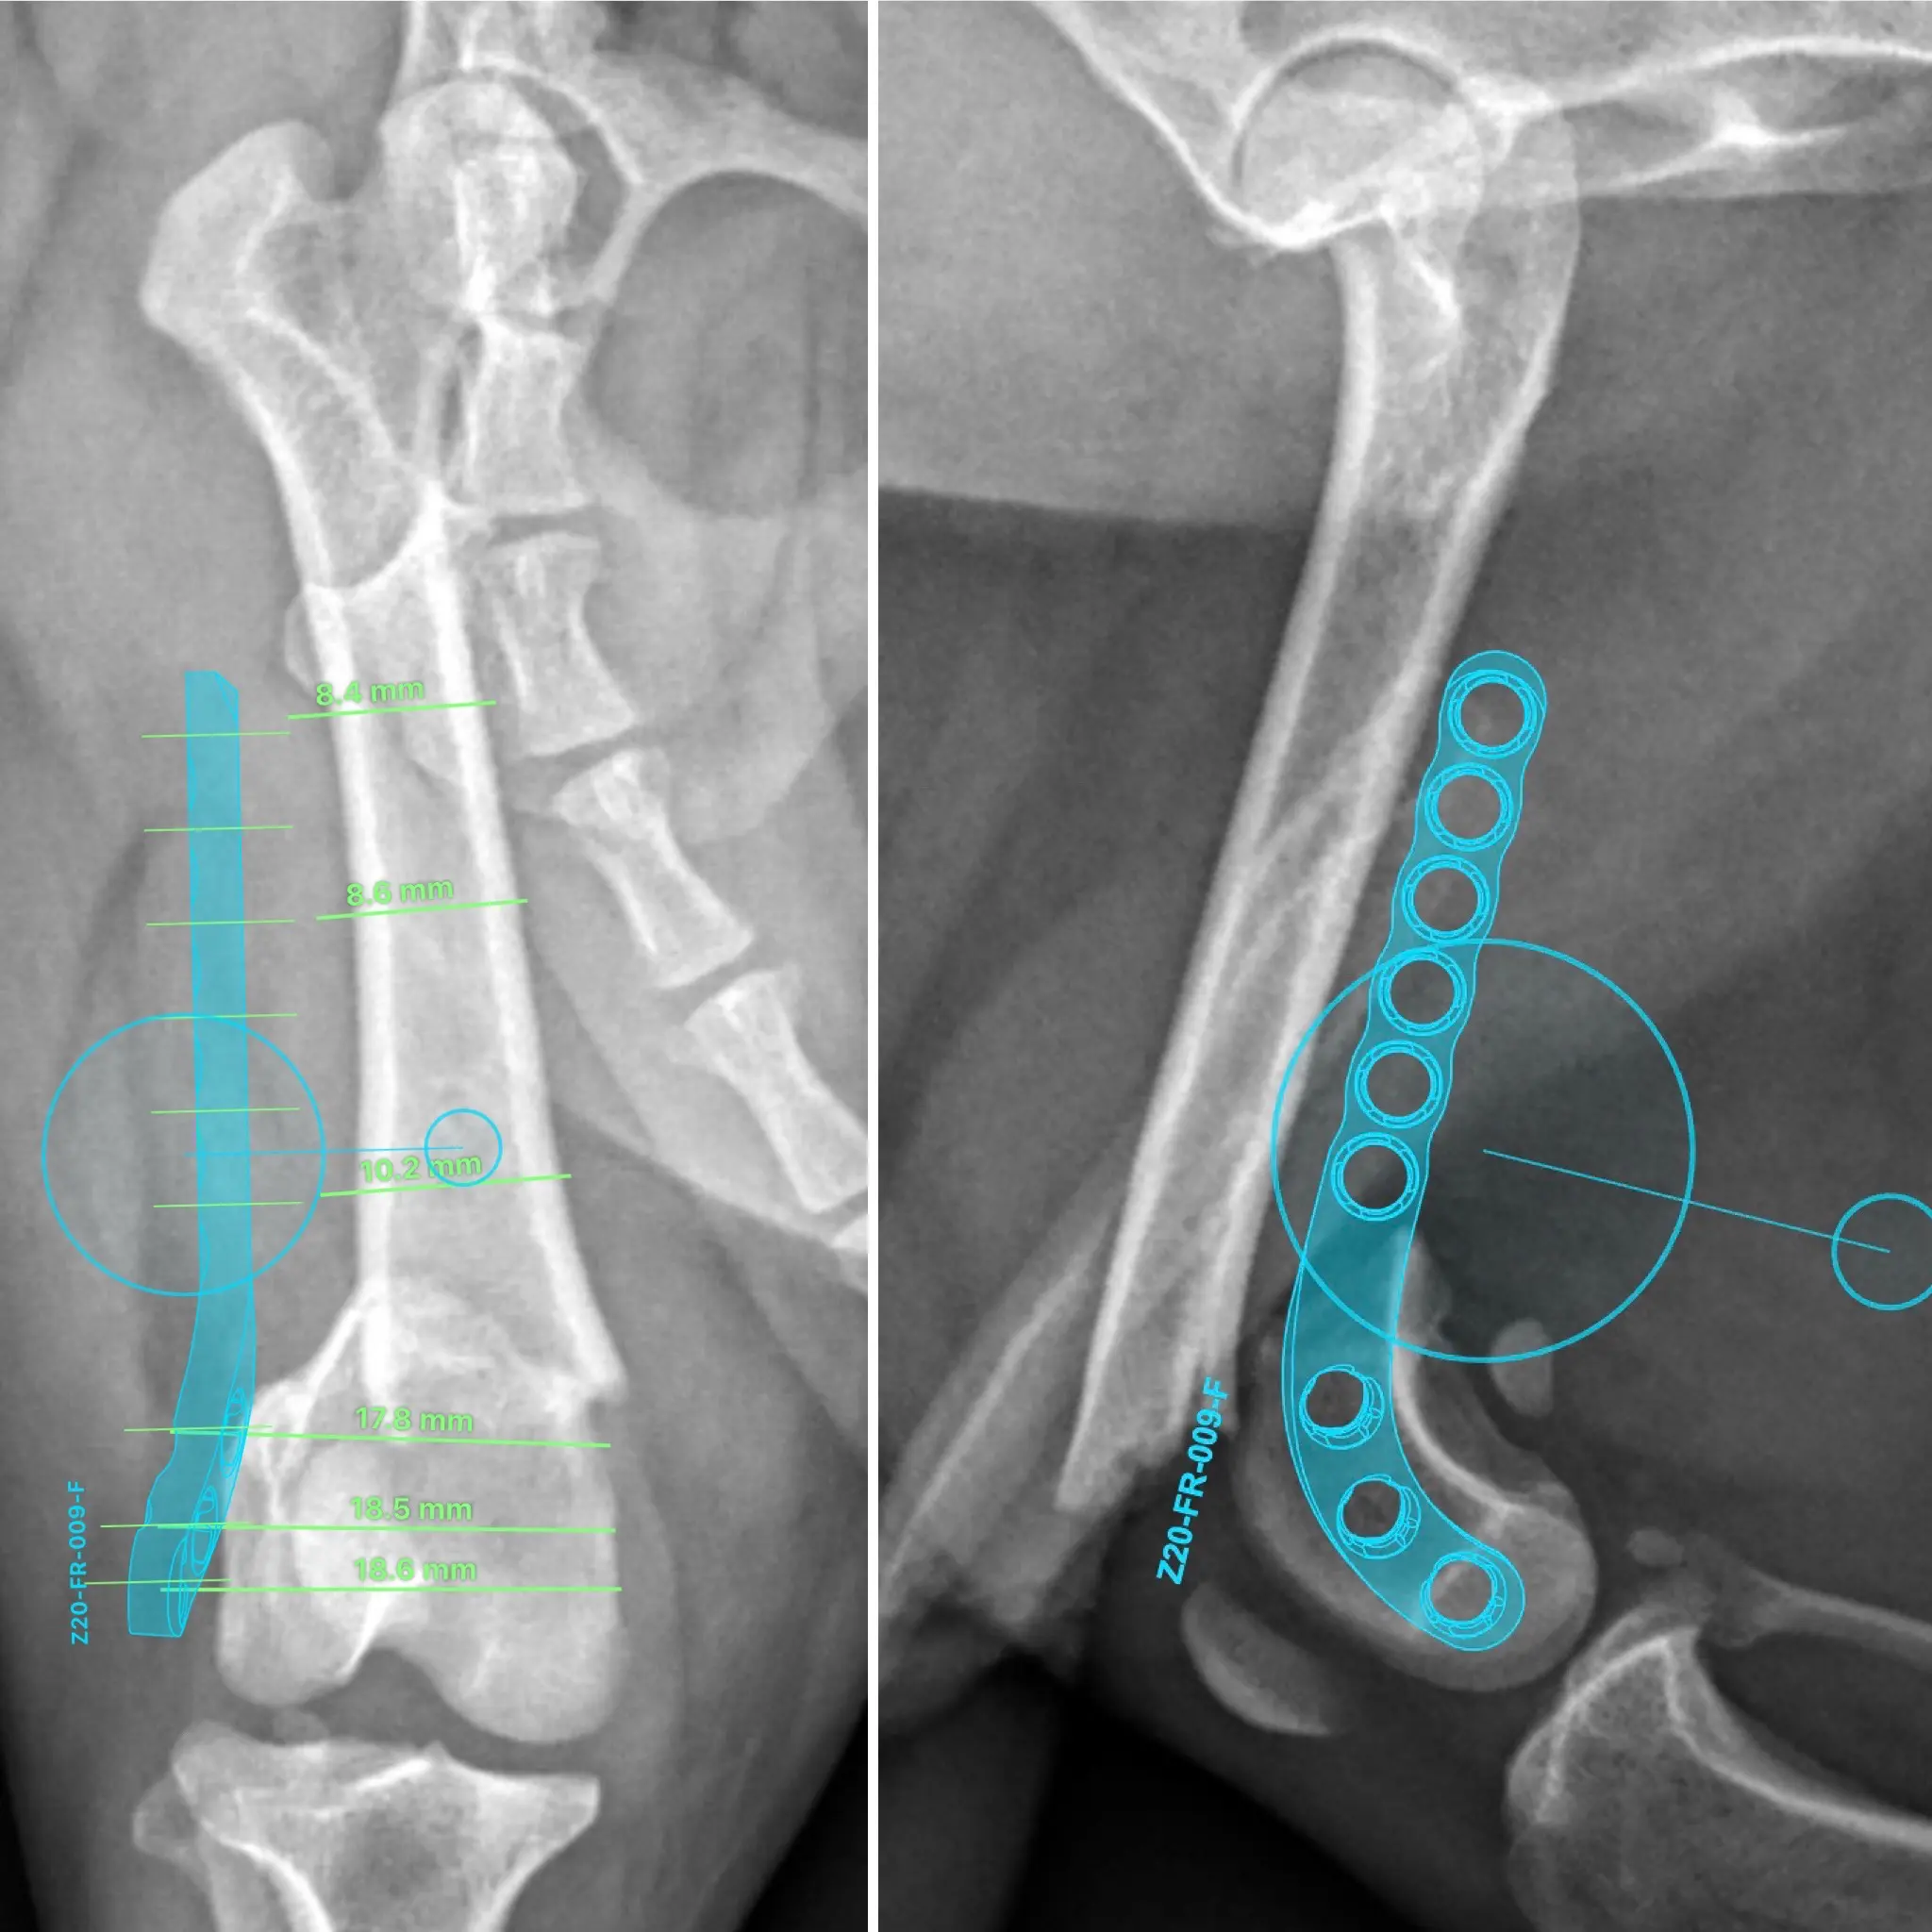

“LEO”. Osteosarcoma de radio manejado mediante técnica Limb Sparing.

“Leo” es un Mastín Español de 5 años de edad y 64 kg de peso, que se presentó en nuestra consulta con historia de cojera